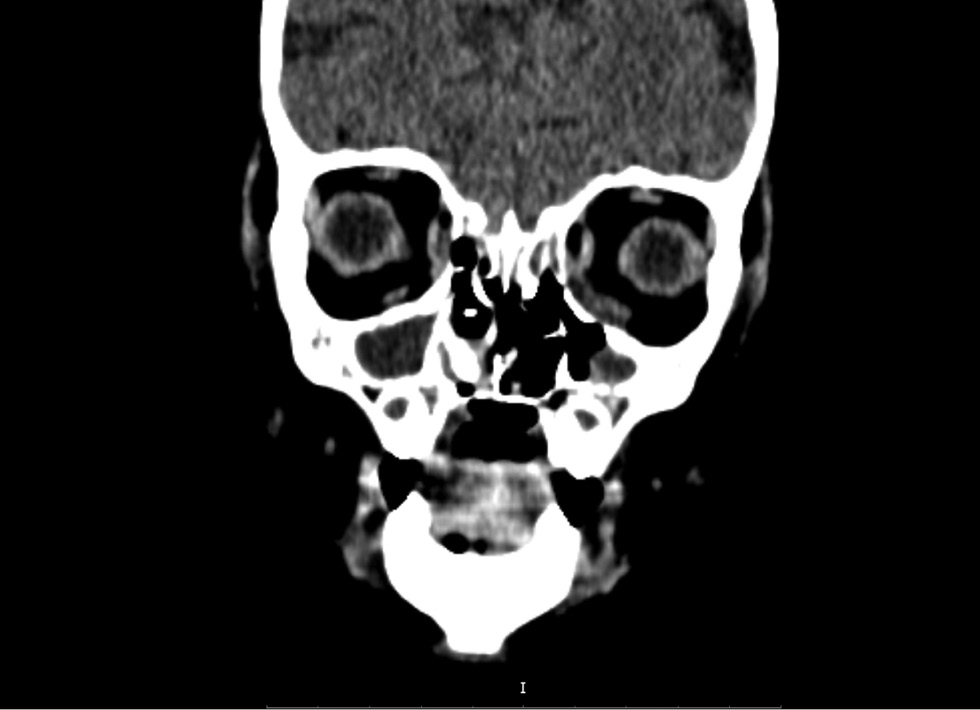

Повторная РКТ на 20-й день госпитализации показала признаки множественных очагов деструкции медиальных стенок орбит, костей носовой полости, твёрдого нёба, альвеолярных отростков верхнечелюстной кости, дефект мягкого неба. Таким образом, было больше данных, свидетельствующих о некротических изменениях, субпериостальный абсцесс крылонебной ямки и орбиты (рис. 2). Появился гиподенсивный очаг в правой лобной доле (энцефалит?) (рис. 3).

Рис. 2. Рентгеновская компьютерная томография орбит, придаточных пазух носа, головного мозга на 20-й день госпитализации.

Fig. 2. X-ray computed tomography of the orbits, paranasal sinuses, and brain on day 20 of hospitalization.

Рентгеновскую компьютерную томографию проводили в динамике на 36, 47, 63-й дни госпитализации. РКТ орбит и придаточных пазух носа выявила признаки множественных обширных очагов деструкции медиальных стенок орбит, костей носовой полости, твёрдого нёба, альвеолярных отростков верхнечелюстной кости, дефект мягкого нёба (рис. 4, 5). С помощью магнитно-резонансной томографии орбит, придаточных пазух носа, головного мозга на 63-й день госпитализации обнаружены признаки множественных обширных очагов деструкции медиальных стенок орбит, костей носовой полости, твёрдого нёба, альвеолярных отростков верхнечелюстной кости, дефект мягкого нёба (рис. 6, 7).

Рис. 4. Рентгеновская компьютерная томография орбит, придаточных пазух носа, головного мозга на 36-й день госпитализации.

Fig. 4. X-ray computed tomography of the orbits, paranasal sinuses, and brain on day 36 of hospitalization.

Отмечалось молниеносное развитие некротических изменений мягких и костных тканей риноорбитальной области с 9-го по 20-й день госпитализации. На 9-й день на рентгеновской компьютерной томограмме обнаружено только истончение медиальной стенки левой орбиты. На 20-й день выявлены множественные очаги деструкции костей орбит и придаточных пазух носа. Даже небольшое промедление в проведении хирургического лечения и отказ от проведения некрэктомии, связанные с прогрессивно ухудшающимся общим состоянием ребёнка и высоким риском анестезии на фоне респираторного и инфекционно-токсического синдрома, сыграли роковую роль в судьбе пациента.